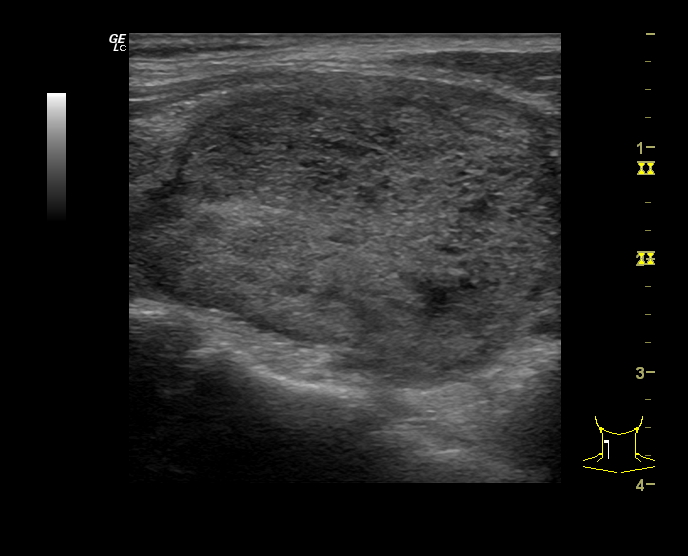

Hallazgos ecográficos

Se estudia la glándula tiroidea mediante sonda lineal de alta frecuencia, realizando cortes transversales y longitudinales. A nivel del lóbulo tiroideo derecho se objetiva un nódulo sólido, con forma «más ancho que alto», isoecoico, con zonas heteroecoicas de 2,4 x 3,4 cm (figura 1), que presenta una lobulación en su margen interno (figura 2), con halo periférico incompleto y vascularización mixta, principalmente periférica (figura 3). No se observan calcificaciones ni adenopatías patológicas. Adyacente al mismo, otro nódulo milimétrico (figura 4), de similares características.